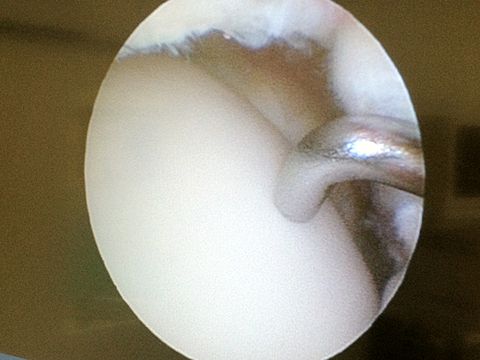

zuerst einmal zu deiner Diagnose. Ein Knorpelschaden Grad 4 wird im MRT oder arthroskopisch diagnostiziert. Wirklich sicher sein kannst du dir bei der Arthroskopie, also wenn jemand in mikrochirurgisch dein Gelenk schaut und den Knorpel optisch und mit einem Tasthaken begutachtet. Grad 4 bedeutet, dass an dieser Stelle der Knochen praktisch frei liegt. Ebenso entscheidet wie der Grad der Schädigung ist aber auch das Ausmaß des Schadens, die Lokalisation, das Körpergewicht und die Symptome.